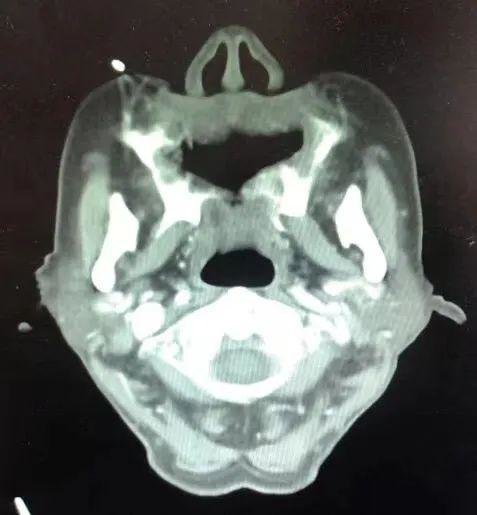

如今已经完全没有肿瘤了

治疗结束后,宋奶奶将跟随家人返回家乡,共同度过新年。医生将继续定期评估她的情况,看是否需要下一步的治疗。目前主要以复查为主,同时进行远期维护,随时关注患者的身体情况。